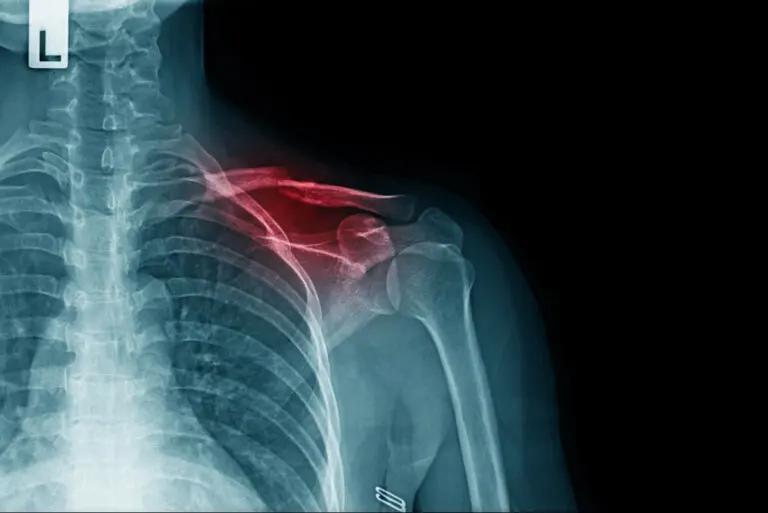

La fractura de clavícula es una de las lesiones óseas más frecuentes. Consiste en la rotura parcial o total de dicho hueso que se encuentra en la parte superior del tórax. Es fundamental para poder mover de forma adecuada el brazo.

La clavícula es un hueso con forma de S que conecta el esternón con el omóplato. Es decir, une el hombro con el tronco, haciendo posible el movimiento del brazo. Tenemos dos clavículas: una izquierda y otra derecha.

Tal y como explican los especialistas de Cochrane, la fractura de clavícula es uno de los tipos más frecuentes de rotura ósea. En concreto, se suele fracturar por el tercio medio. La mayor incidencia se produce en adultos jóvenes y niños.

La prueba complementaria que más se utiliza para ayudar al diagnóstico es la radiografía. Con ella se puede observar la línea de fractura y la disposición de los huesos. Sin embargo, en algunos casos pueden ser necesarias otros estudios más específicos, como la tomografía computarizada.